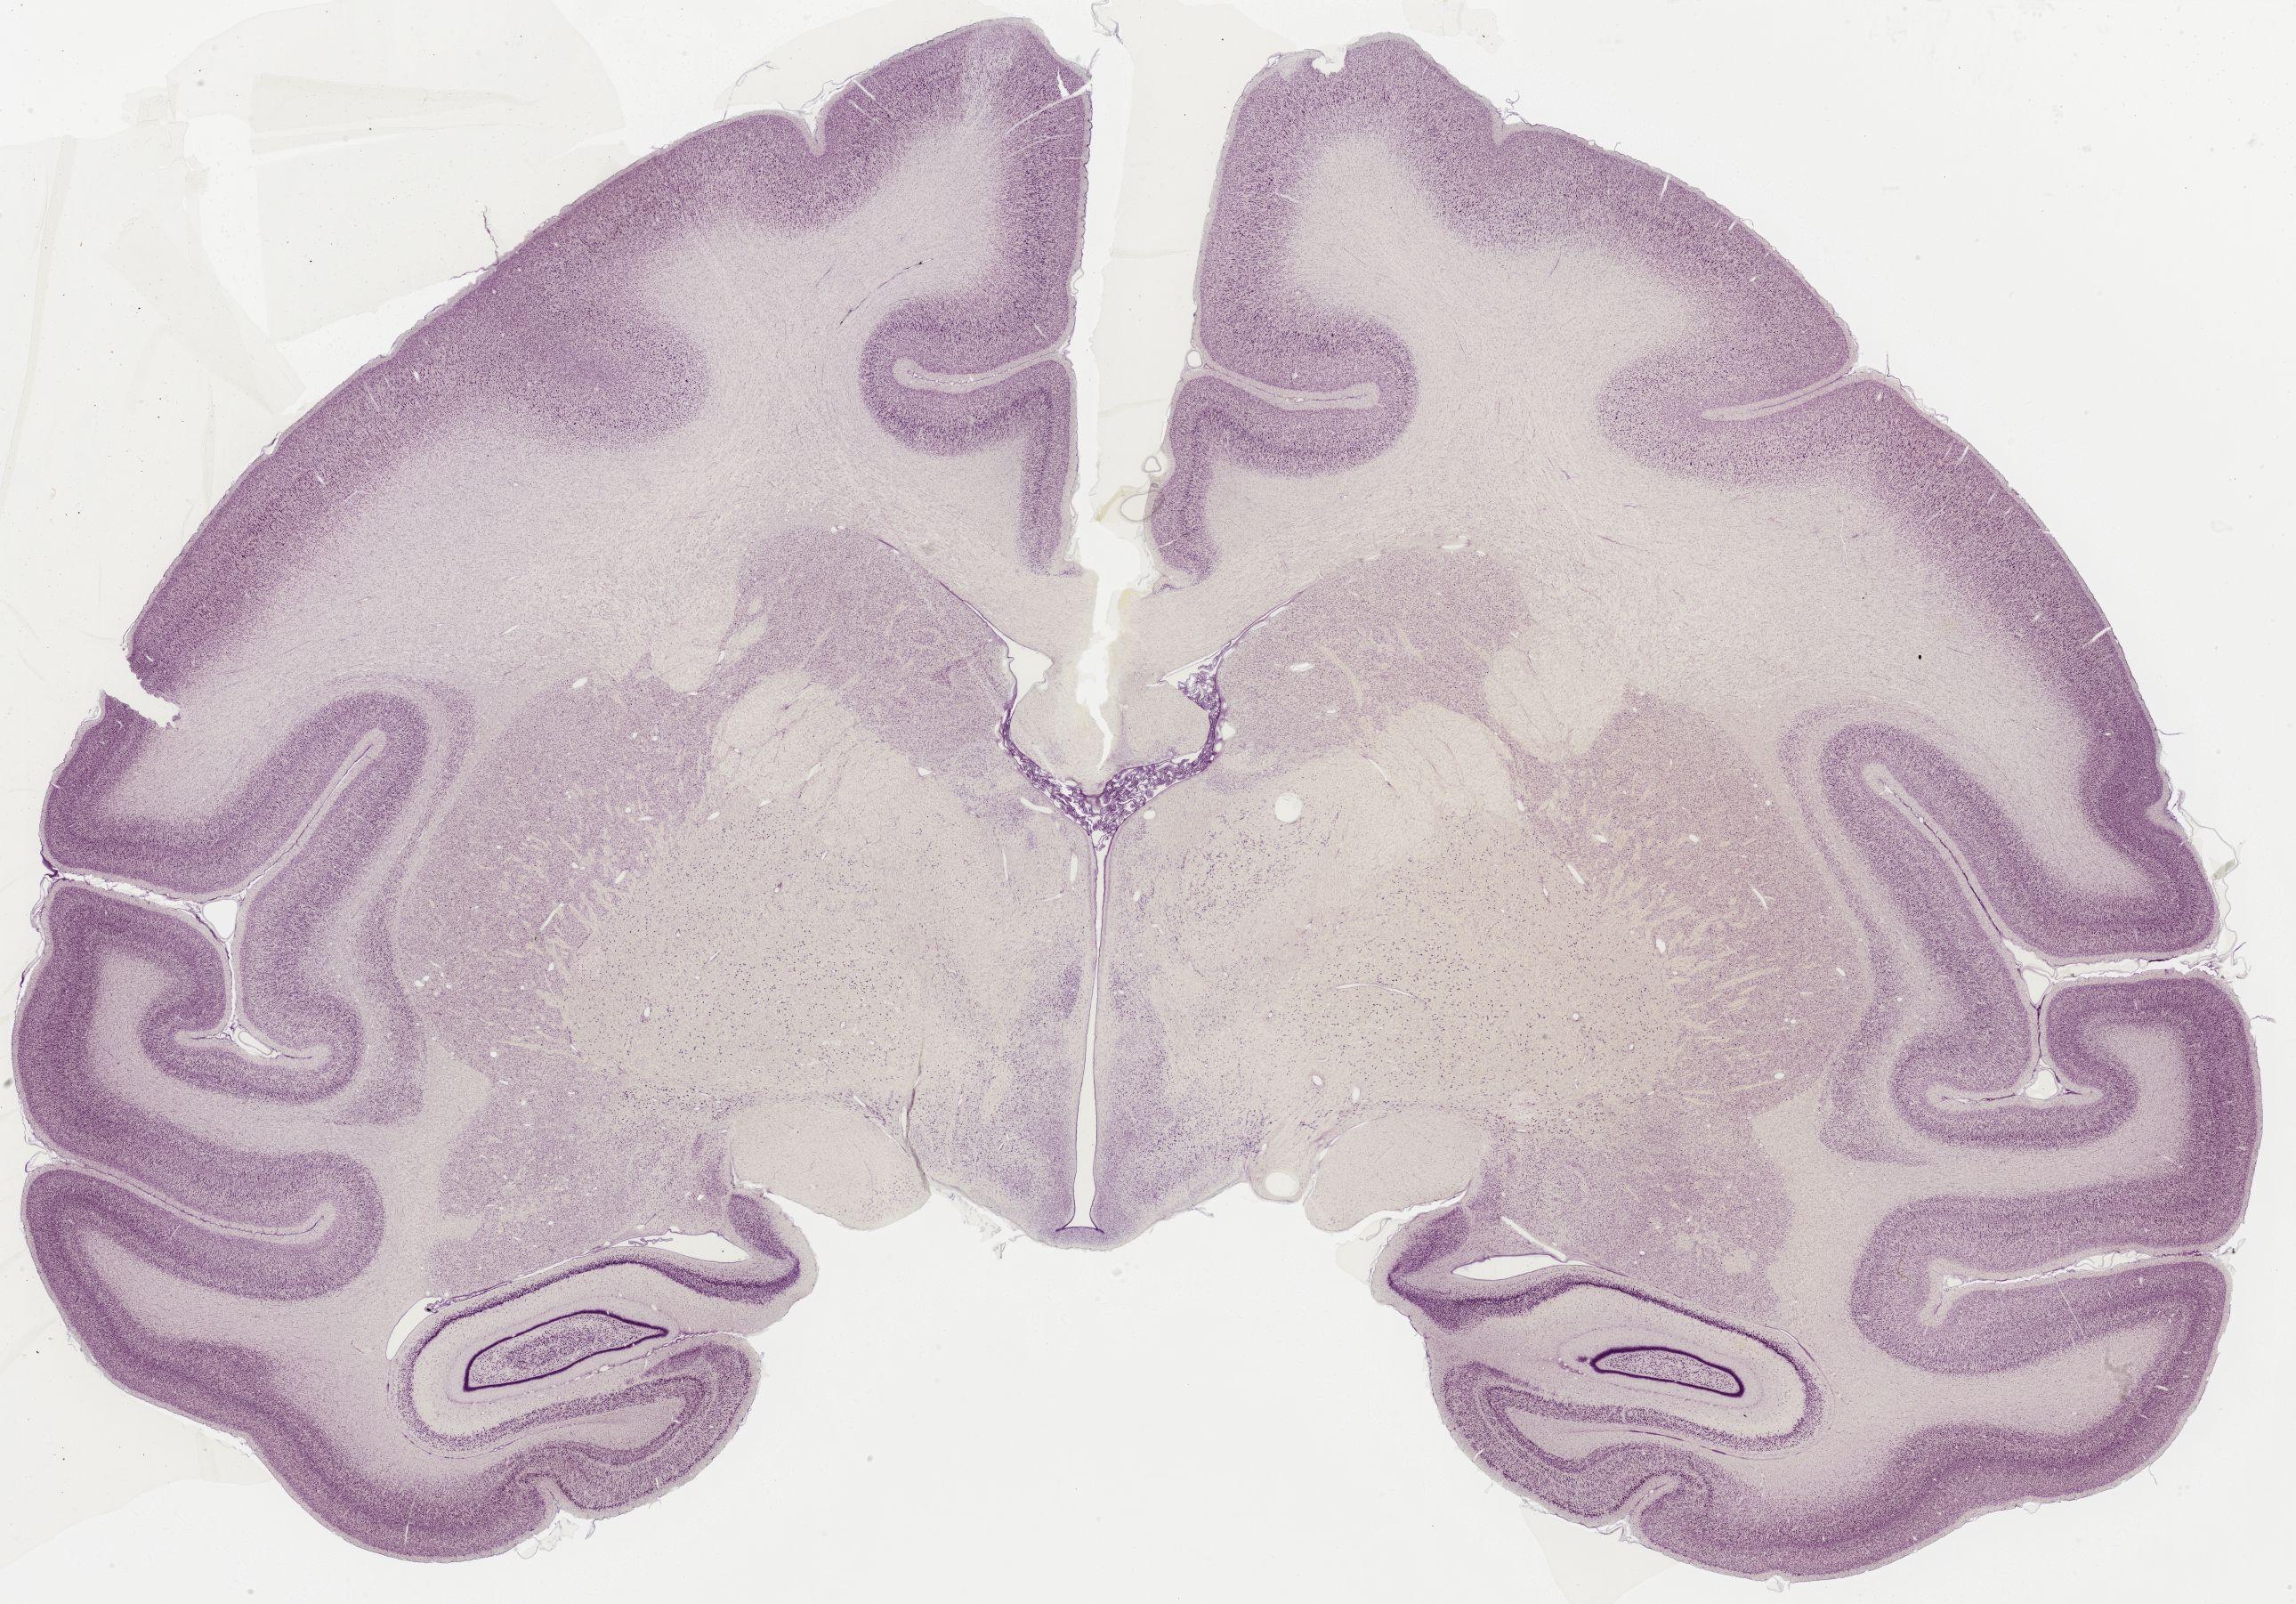

Datasets -> Macaca Mulatta -> Nissl, coronal, histo, Whole-Brain, adult [ Metadata ] · Source: Edward G. JonesDisplaying Sections 1 thru 40 of 56 Sections for this DatasetPages: 1 2 1339 - labeled 1301 - labeled 1251 - labeled 1201 - labeled 1151 - labeled 1102 - labeled 1051 - labeled 1040 - labeled 1020 - labeled 1006 - labeled 1001 - labeled 0982 - labeled 0975 - labeled 0958 - labeled 0951 - labeled 0941 - labeled 0924 - labeled 0920 - labeled 0901 - labeled 0894 - labeled 0878 - labeled 0875 - labeled 0859 - labeled 0851 - labeled 0845 - labeled 0824 - labeled 0823 - labeled 0801 - labeled 0800 - labeled 0785 - labeled 0781 - labeled 0771 - labeled 0770 - labeled 0732 - labeled 0721 - labeled 0720 - labeled 0701 - labeled 0682 - labeled 0680 - labeled 0666 - labeledPages: 1 2